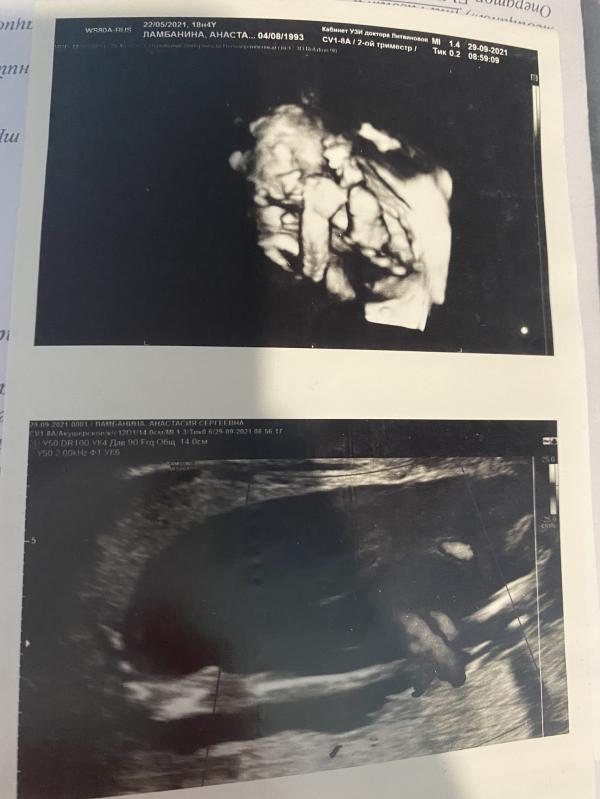

➿Обвитие - да, до 30 недели -одинарное, после двойное

🐥Срок на момент родов - 35,6недель по ПДР, по первому узи 36,5 недель

⚖️Вес -3650 (если в срок, то обещали не меньше 4200)

📐Рост - 55 см

📈Апгар - 7/8